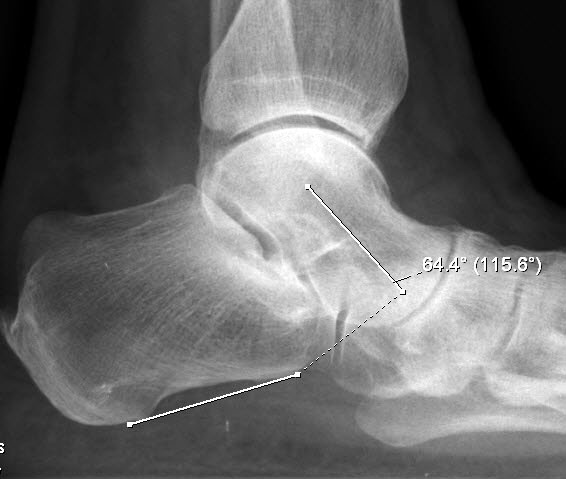

Konventionelles Röntgen

Stehende konventionelle Röntgenbilder eines Fußes mit Planovalgus Deformität Stadium II b dorsoplantar (dp) und seitlich. Auf der dp-Aufnahme zeigt sich die talo-calcaneare Divergenz, der gegenüber dem Kalkaneus nach anterior gleitende Talus und d

Stehende Aufnahmen des Fußes dorsoplantar (dp) und seitlich sowie des OSG anteroposterior (ap) sind die Grundlage der konventionellen Röntgendiagnostik (Abb. 5). Ergänzend werden gelegentlich die Rückfuβ-Alignement Aufnahme nach Saltzman 19 und Vergleichsaufnahmen der Gegenseite durchgeführt.

Auf der seitlichen, stehenden Aufnahme des Fußes wird ebenfalls der laterale Talo-Metatarsale I Winkel (Abb. 6 d) gemessen und so das kollabierte mediale Längsgewölbe dokumentiert. Auch hier gilt ein Talo-Metatarsale I Winkel von > 5° (nach plantar konvex) als pathologisch 21. Der Kollaps findet dabei meist im Talonaviculargelenk, seltener in der Naviculocuneiform-Gelenkreihe statt. Instabilität und Arthrose im 1. TMT sollten ausgeschlossen oder bei der Operationsplanung mit einbezogen werden. Weitere wichtige radiologische Messungen zur Beurteilung der Planovalgus-Statik und Progression der Deformität sind der laterale talo-calcaneare Winkel (Abb. 6 e) und der Abstand des Os cuneiforme-Unterrandes zum Untergrund (Abb. 6 f, Cuneiform height, 22. Eine anteriore Translation des Talus auf dem Kalkaneus findet man sowohl auf der ap, als auch auf der seitlichen Aufnahme des Fuβes mit Aufhebung der Cima-Linie.